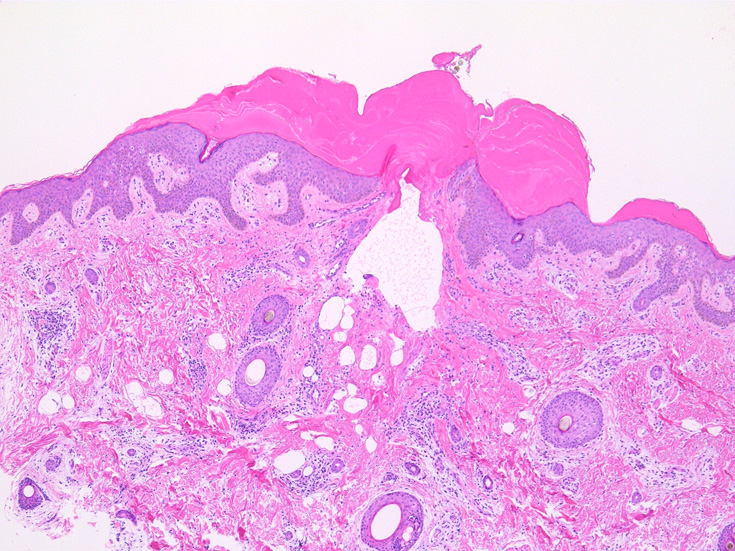

IWT-case01 66yo male. 3週間前(!)南アルプスに登山. 腹部皮膚のイボ様腫瘤に気づき来院。

マダニと思われる虫体を皮膚ごと切除した。

(case02の皮膚表面にみられる硝子様の層がそれに相当するようです。)